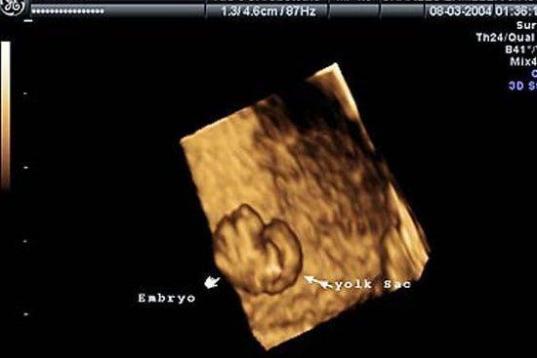

En esta galería puedes ver en fotos como es el desarrollo de un feto de semana en semana:

Desarrollo del feto, en fotos